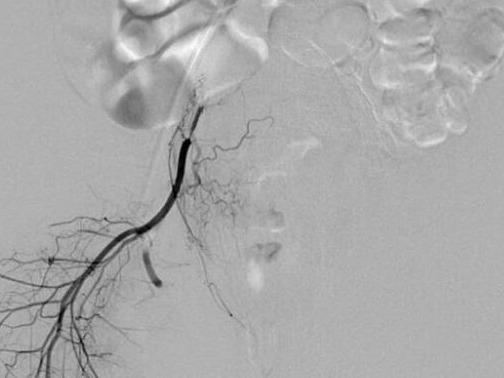

经过检查,医生发现小段体温达到39℃,尿中有大量白细胞,被诊断为急性肾盂肾炎。医生仔细询问并分析了小段的生活习惯后,推测其患病的原因是长期憋尿。

“正常排尿不仅能排出体内代谢废物,对泌尿系统也是一次自净”,武汉市第四医院肾内科董骏武主任解释,肾脏每时每刻都在产生尿液,尿液经过输尿管输送到膀胱,在膀胱内储存起来,膀胱充盈后会产生尿意。如果总是憋尿,膀胱里的尿液储存的时间太长了,尿道口的细菌就容易在膀胱里滋生繁殖,甚至可能随着输尿管感染肾脏,造成上尿路感染,也就是肾盂肾炎。